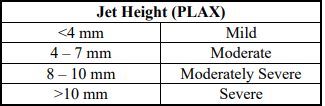

jet height (PLAX)

mild

moderate

moderatley severe

severe